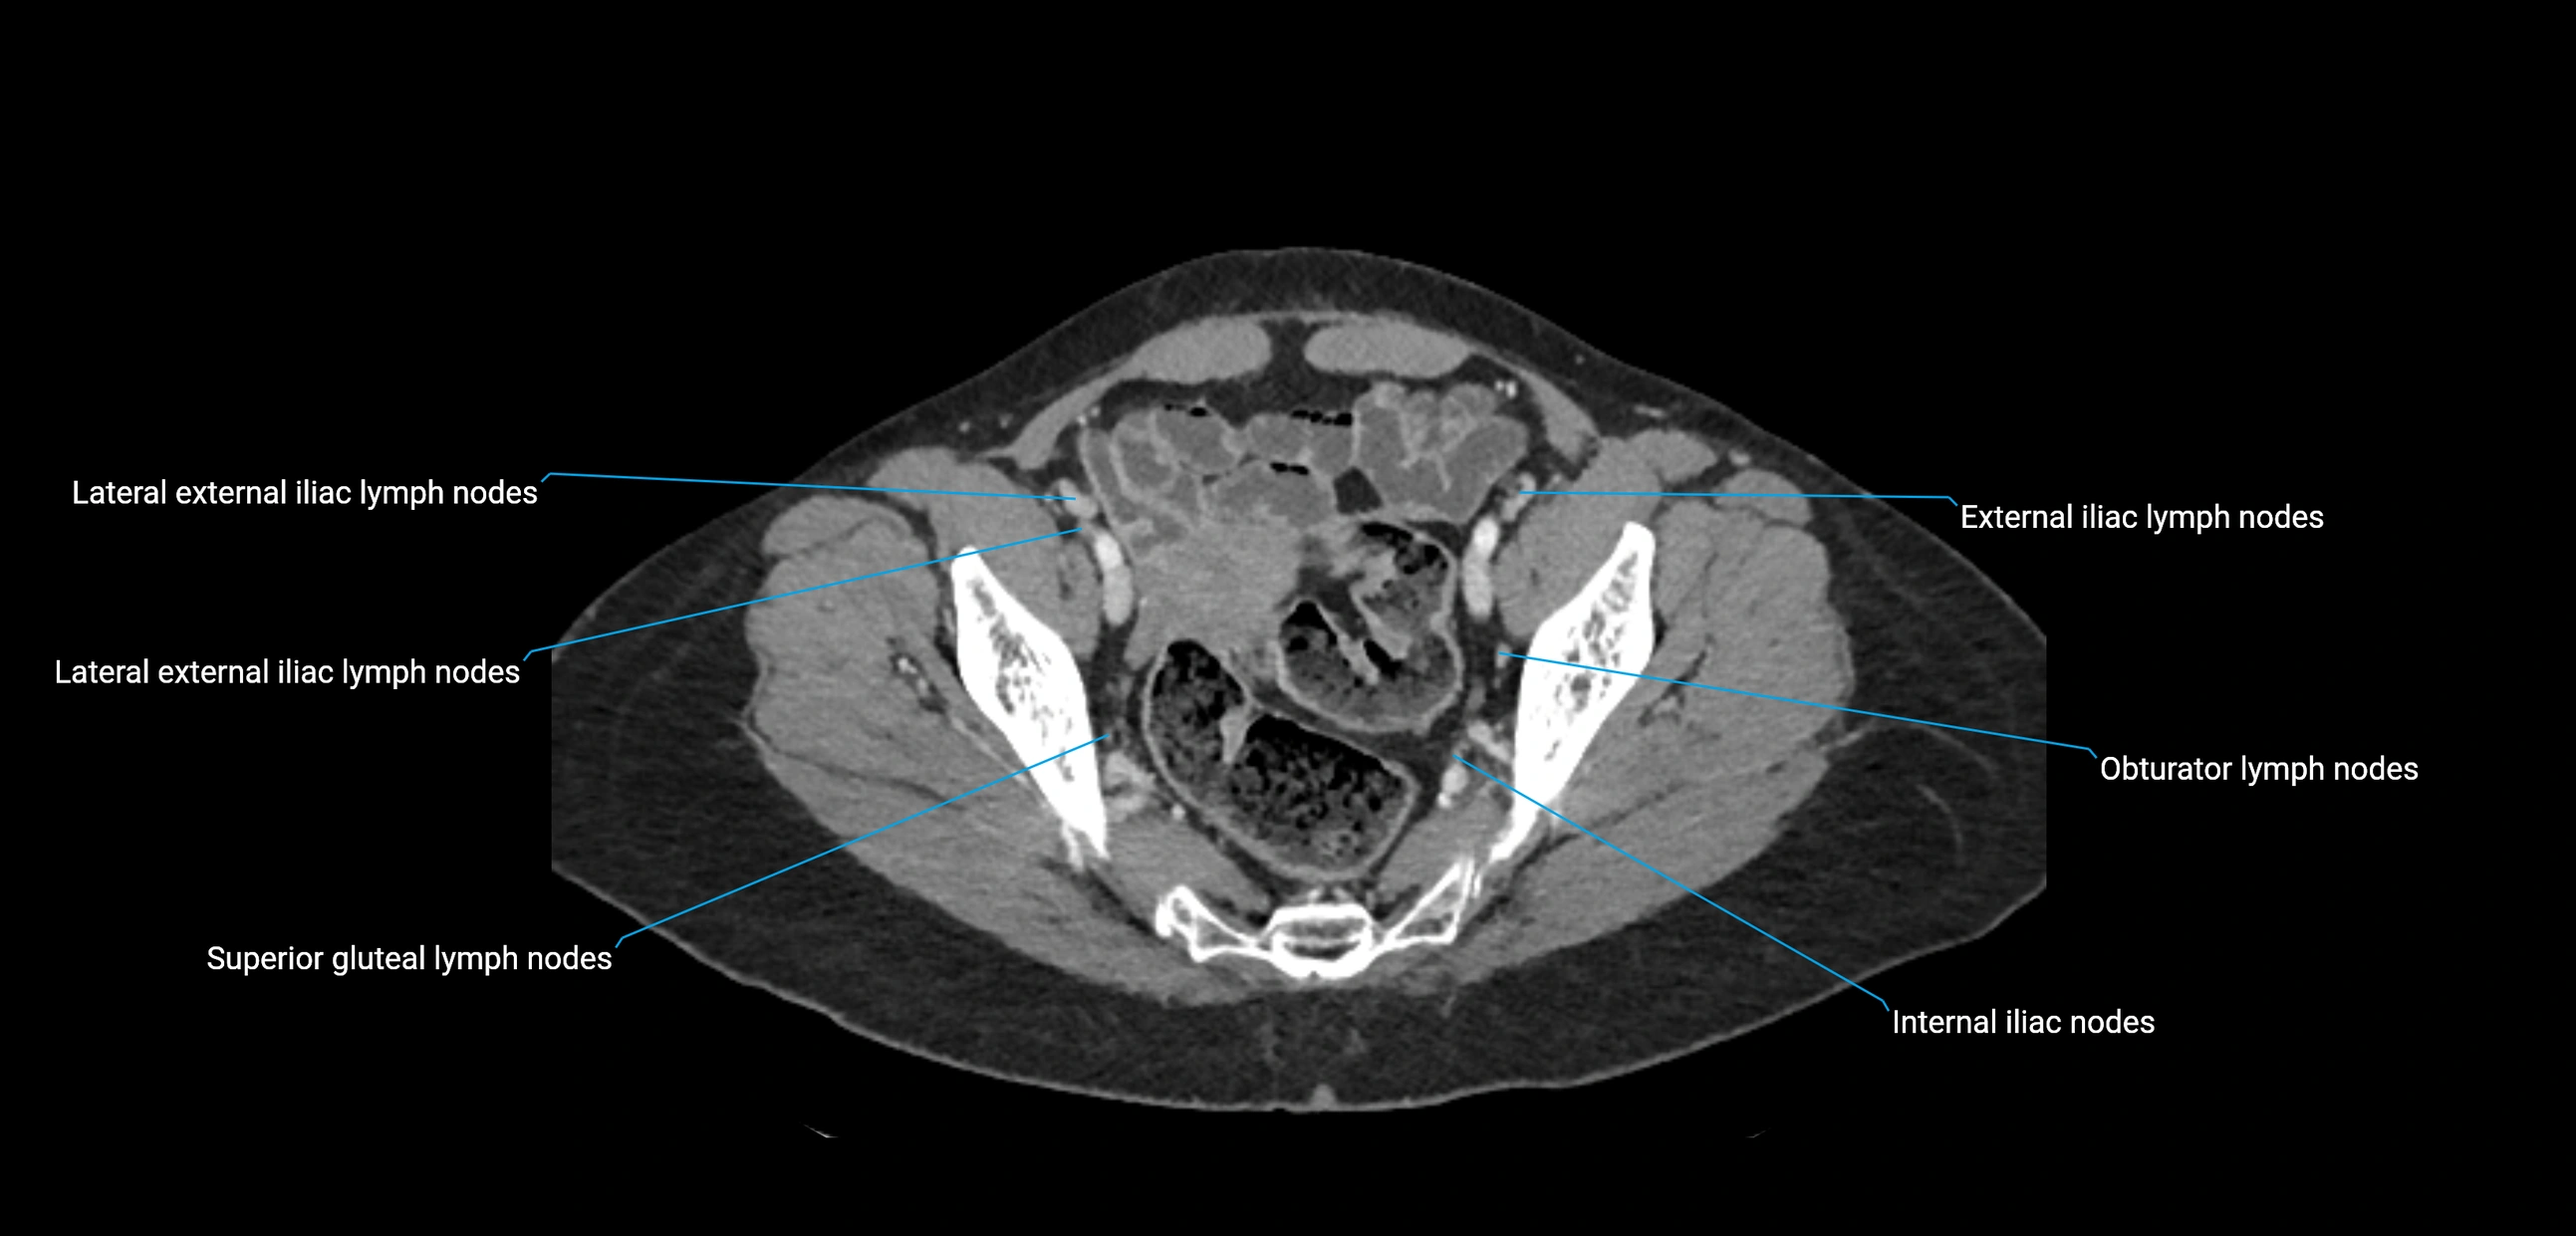

CT Appearance

CT Post-Contrast:

• Normal nodes enhance homogeneously

• Malignant nodes may show heterogeneous enhancement, central necrosis, or conglomerate formation

• Size >1 cm short axis is suspicious, though morphology and distribution are equally important

CT Venography (CTV):

• Demonstrates nodal encasement or compression of adjacent vessels (aorta, IVC, renal veins)

• Useful in staging testicular and ovarian malignancies

• Provides 3D reconstructions for retroperitoneal lymph node dissection planning